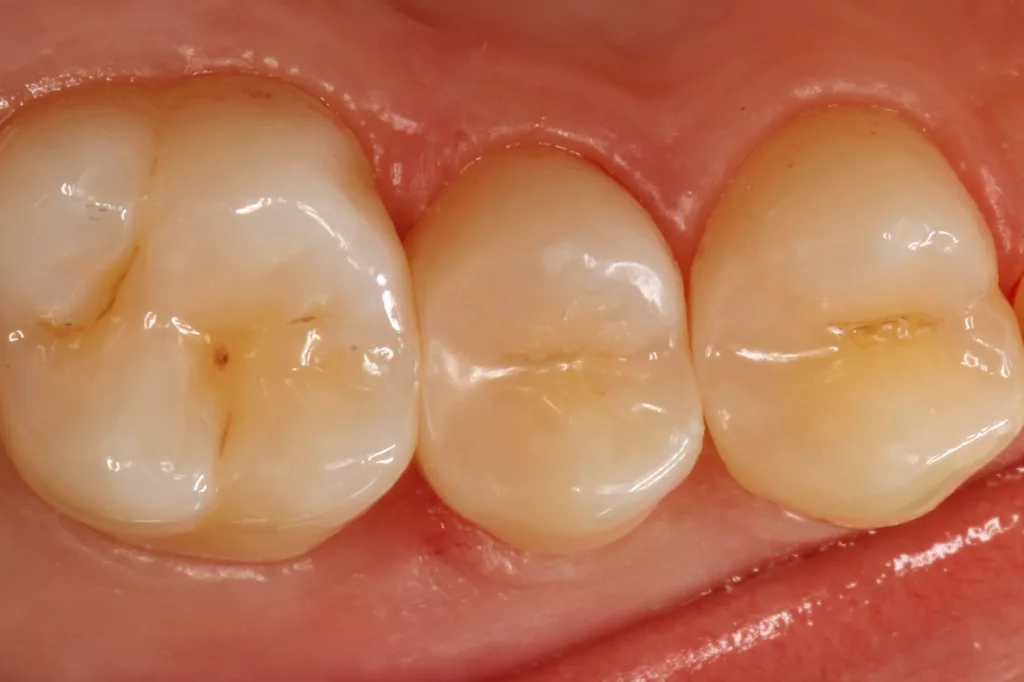

Die Abbildung 10 zeigt das Behandlungsergebnis unmittelbar nach Ausarbeitung und Politur (Diacomp Plus Twist, EVE), die Abbildung 11 bei einer weiteren Kontrolle nach sechs Monaten. In diesem Kontrolltermin wurden dann im routinemäßigen, zwei- bis dreijährigen Intervall Bissflügelröntgenaufnahmen zur Kariesdiagnostik angefertigt. Auf der Röntgenaufnahme zeigt sich die neue Visalys-Bulk-Flow-Restauration als randdicht, anatomisch korrekt geformt und ausreichend röntgenopak (Abb. 12). Die Schmelzläsion mesial an den Zähnen 15 und 16 erschien nicht therapiebedürftig, da die Oberfläche intakt war, wohl aber die versteckte Dentinläsion distal an dem Zahn 15. Der Defekt wurde in einem weiteren Termin identisch mit denselben Materialkombinationen und identischem Polymerisationsprotokoll versorgt (Abb. 13 bis 15).